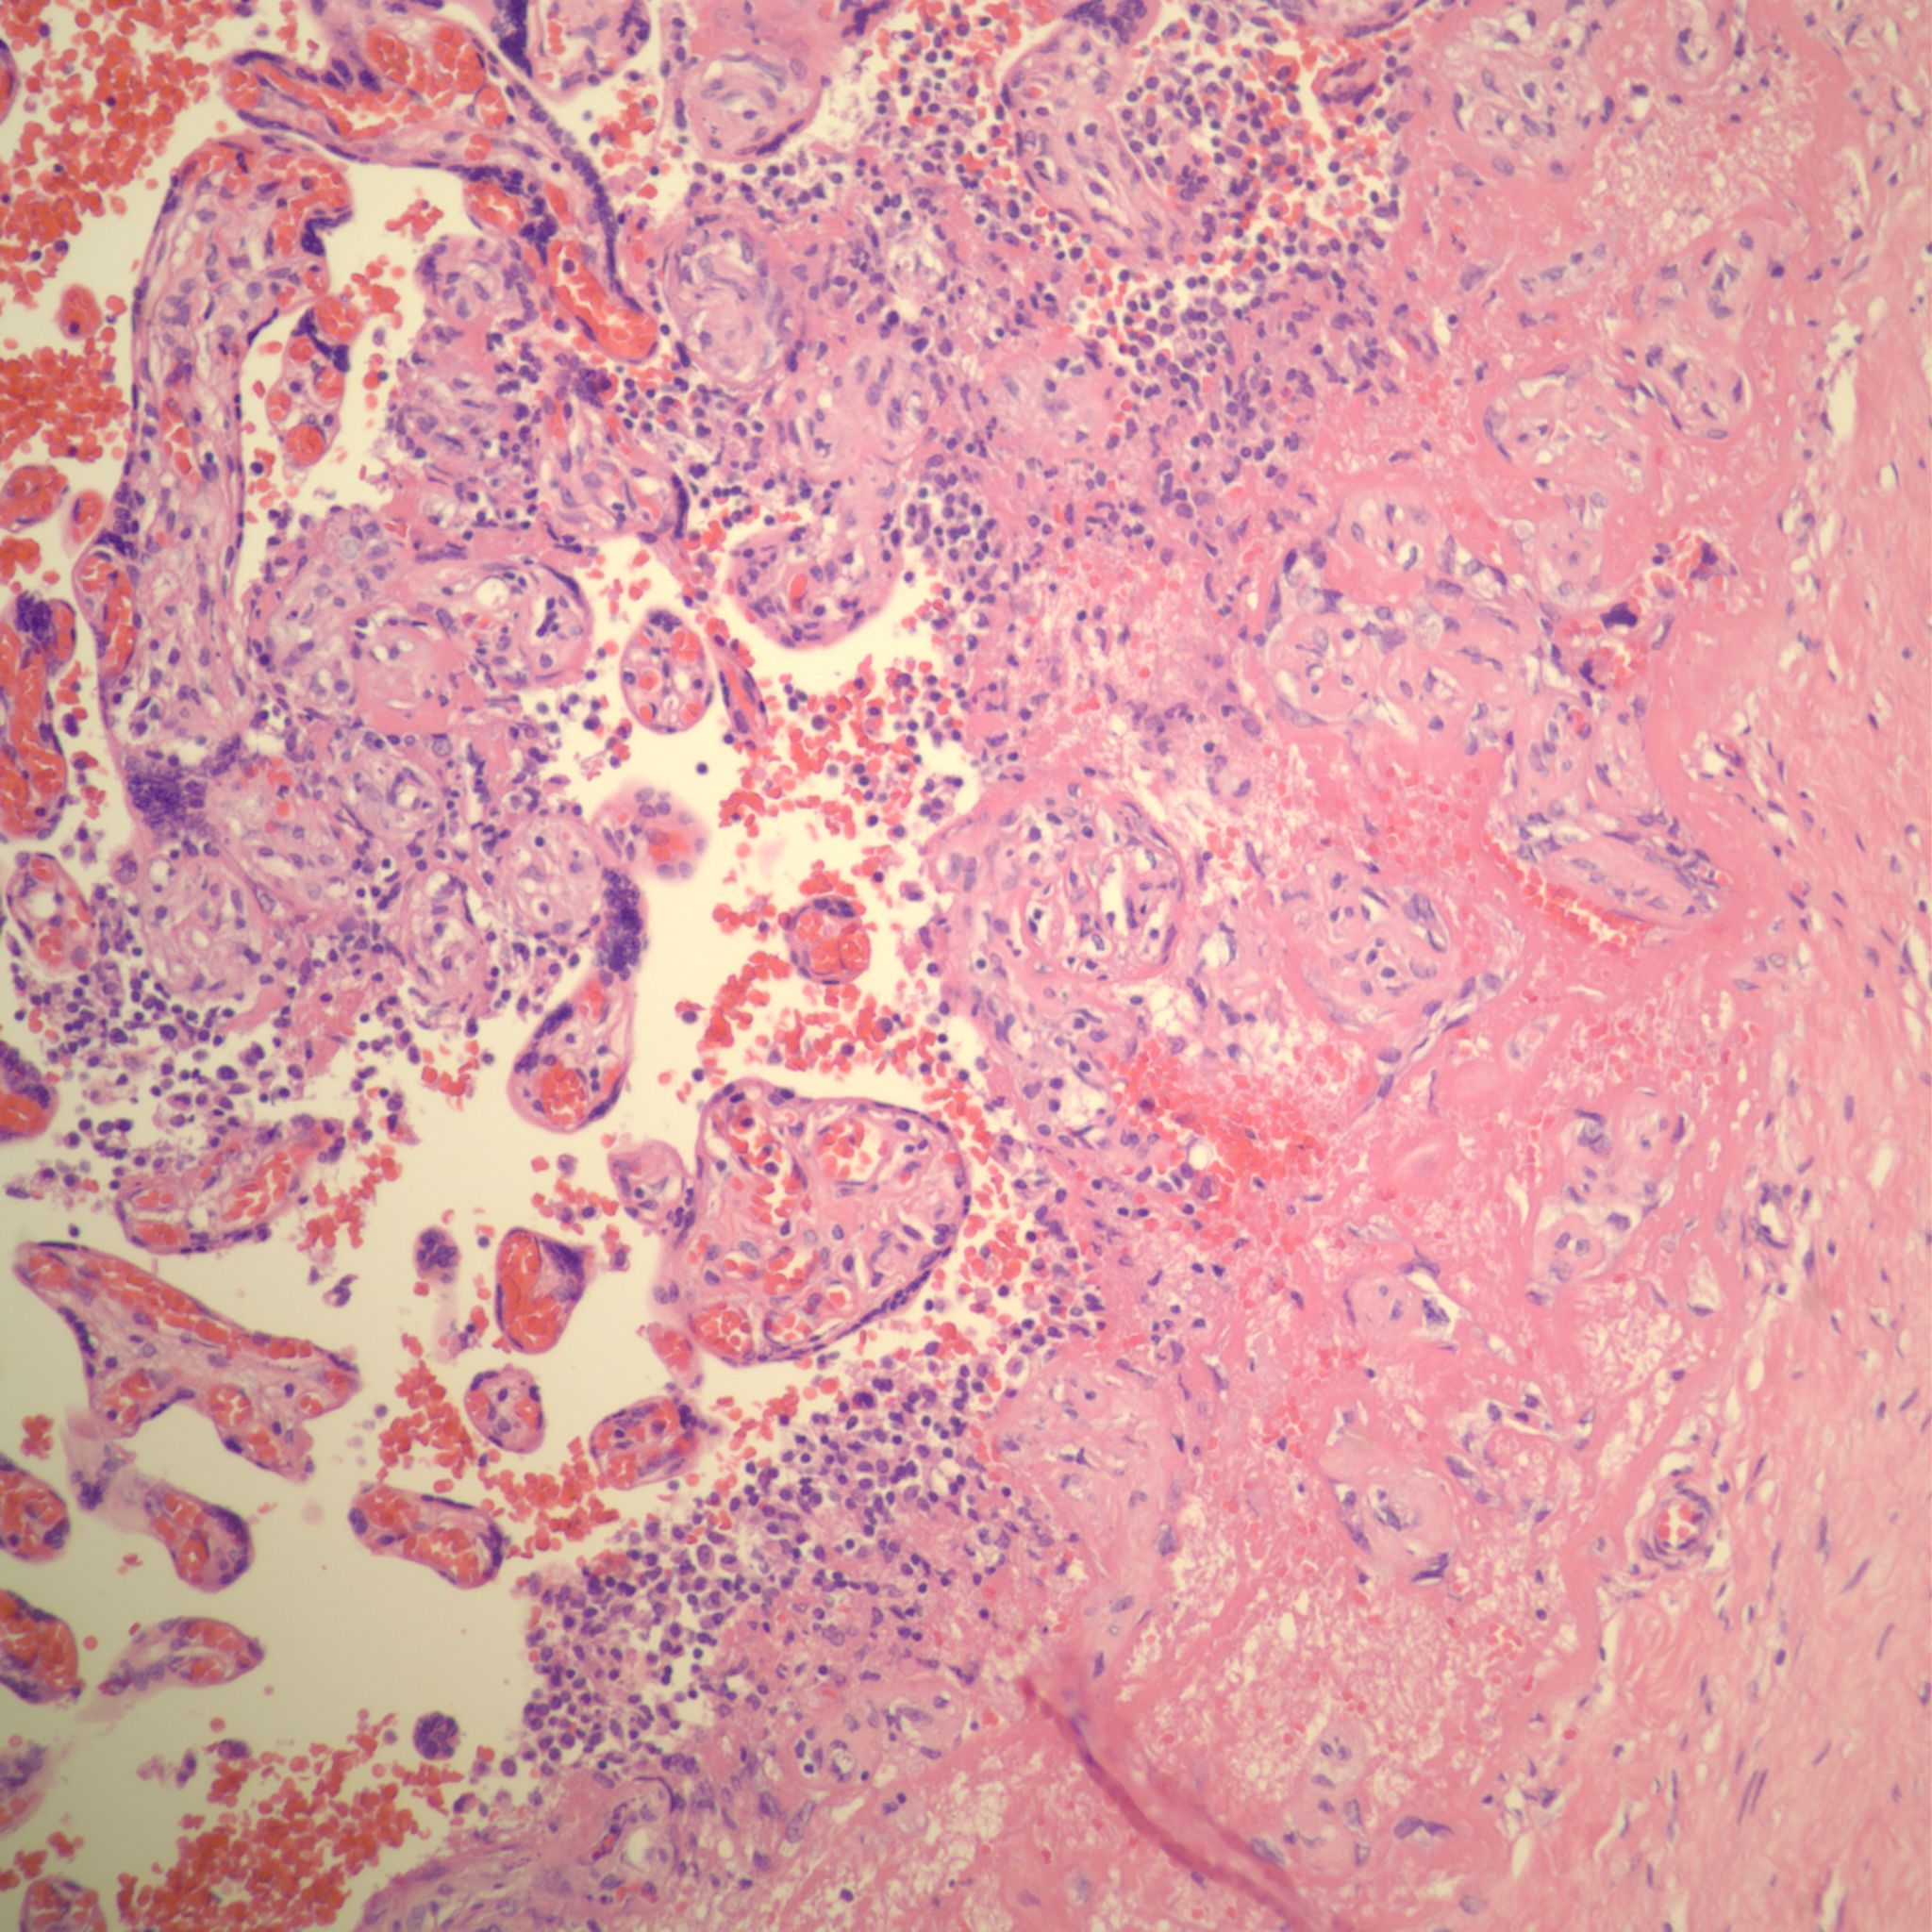

CHIV with prominent perivillous fibrinoid deposition

CHIV associated with Villitis of Uknown Etiology (VUE)

This pattern could be due to a primary cause of VUE with incidental chemotaxis of monocytes, two pathogenetically interrelated processes, or an incidental focus of VUE in a predominant CIIV disease. Currently, describing the extent of each process and its colocalization or lack of may prove useful until a better way to classify the co-existing lesions can be developed. One study has shown that there is a dichotomy between cases with c4d staining and those without c4d staining18.

Perivillous fibrinoid: See entry on perivillous fibrinoid. See pathogenesis below. Some perivillous fibrinoid is a normal finding especially in the subchorionic intervillous space, along septa and adjacent to infarctions. Currently, there are no specific criteria to identify perivillous fibrinoid that is a consequence of syncytiotrophoblast injury from intervillositis. Increased perivillous fibrinoid above normal has been associated with CHIV.

Villitis of Unknown (A)Etiology (VUE): See entry on villitis of unknown aetiology, and pathogenesis below. As with perivillous fibrinoid, the relationship of VUE to the intervillositis is still not understood. Villitis of unknown aetiology villitis, if independent of intervillositis, would be present in the same percentage of cases as in the general population, around 6%. There is both observational evidence and potential pathogenetic relationships between villitis and intervillositis. An association of the two lesions is probable.